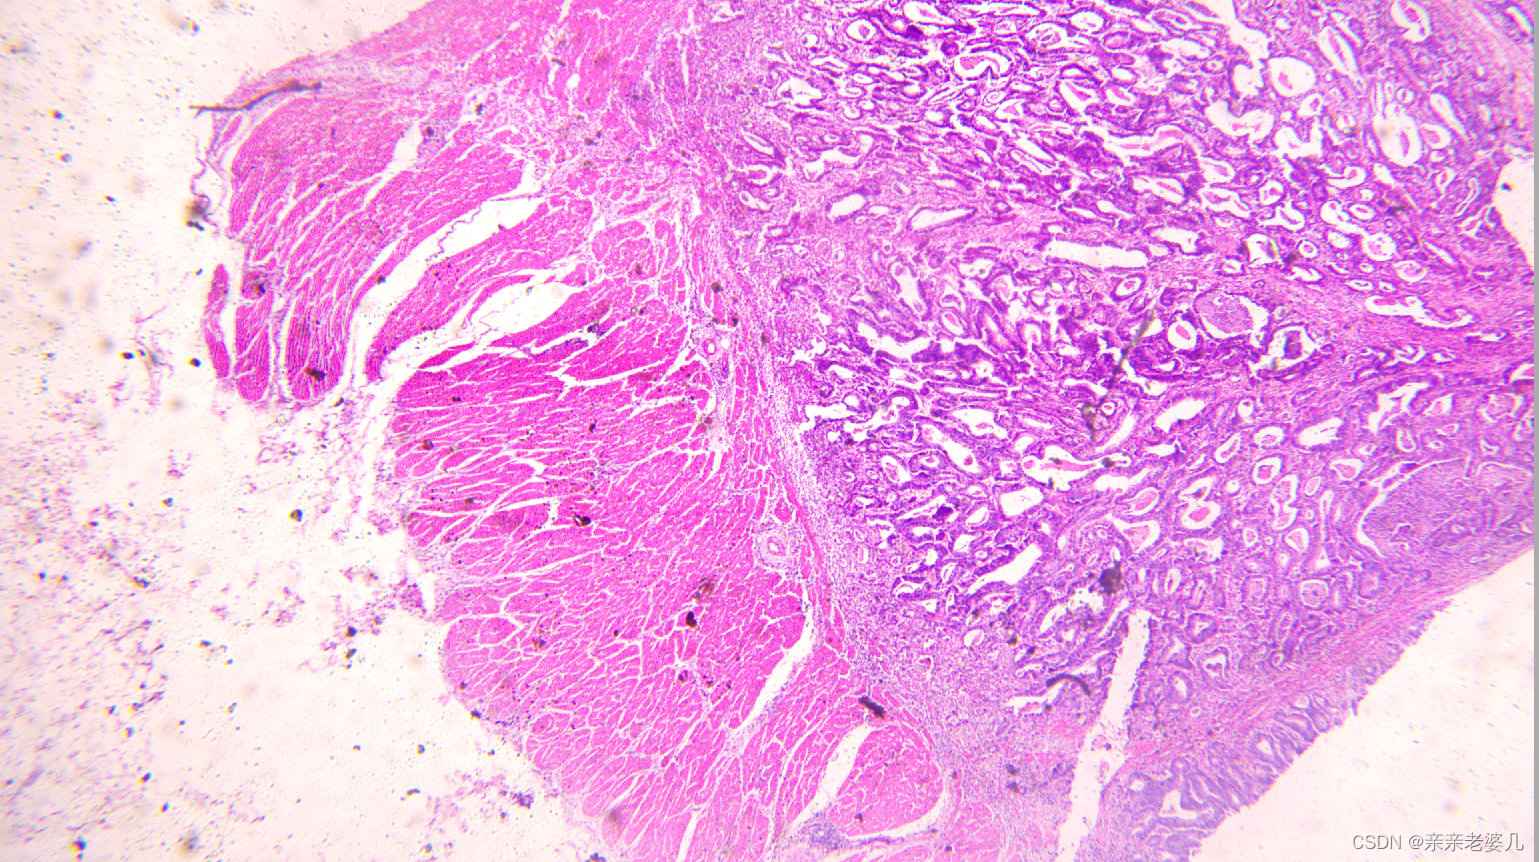

9. 千奇百怪的疾病——疾病的显微诊断及大体实物标本展示

如何获得标本:

手术 取材 包埋 蜡块 切片 染色

肠腺癌

正常大肠